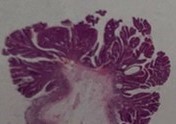

クリスタルバイオレット拡大観察

最大80倍まで拡大観察し、がんの深さを評価します